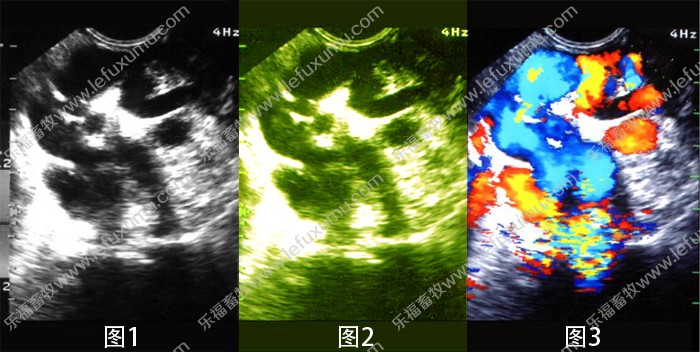

综合以上情况:我们了解的黑白B超(图1),伪彩B超(图2),全彩B超(图3)只是在画面显示上的区别。其实更大的区别在于功能。

黑白B超相当于老式的黑白电视,黑白显示,画面粗糙,信号差,容易受干扰

伪彩B超相当于黑白电视屏上贴一个彩色膜,等同彩色显示。但是功能升级很多,分辨力高了,芯片数字化了。

彩色B超相当于现代化的彩色电视,信号好,抗干扰强,功能强大,图像多彩显示。

简单一句话:全彩B超分辨率,功能等要好于伪彩B超,伪彩B超又好于黑白B超。